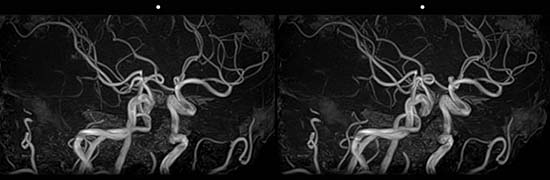

脳の血管 平行法

交差法の得意な人用    平行法が得意な人用    アナグリフ